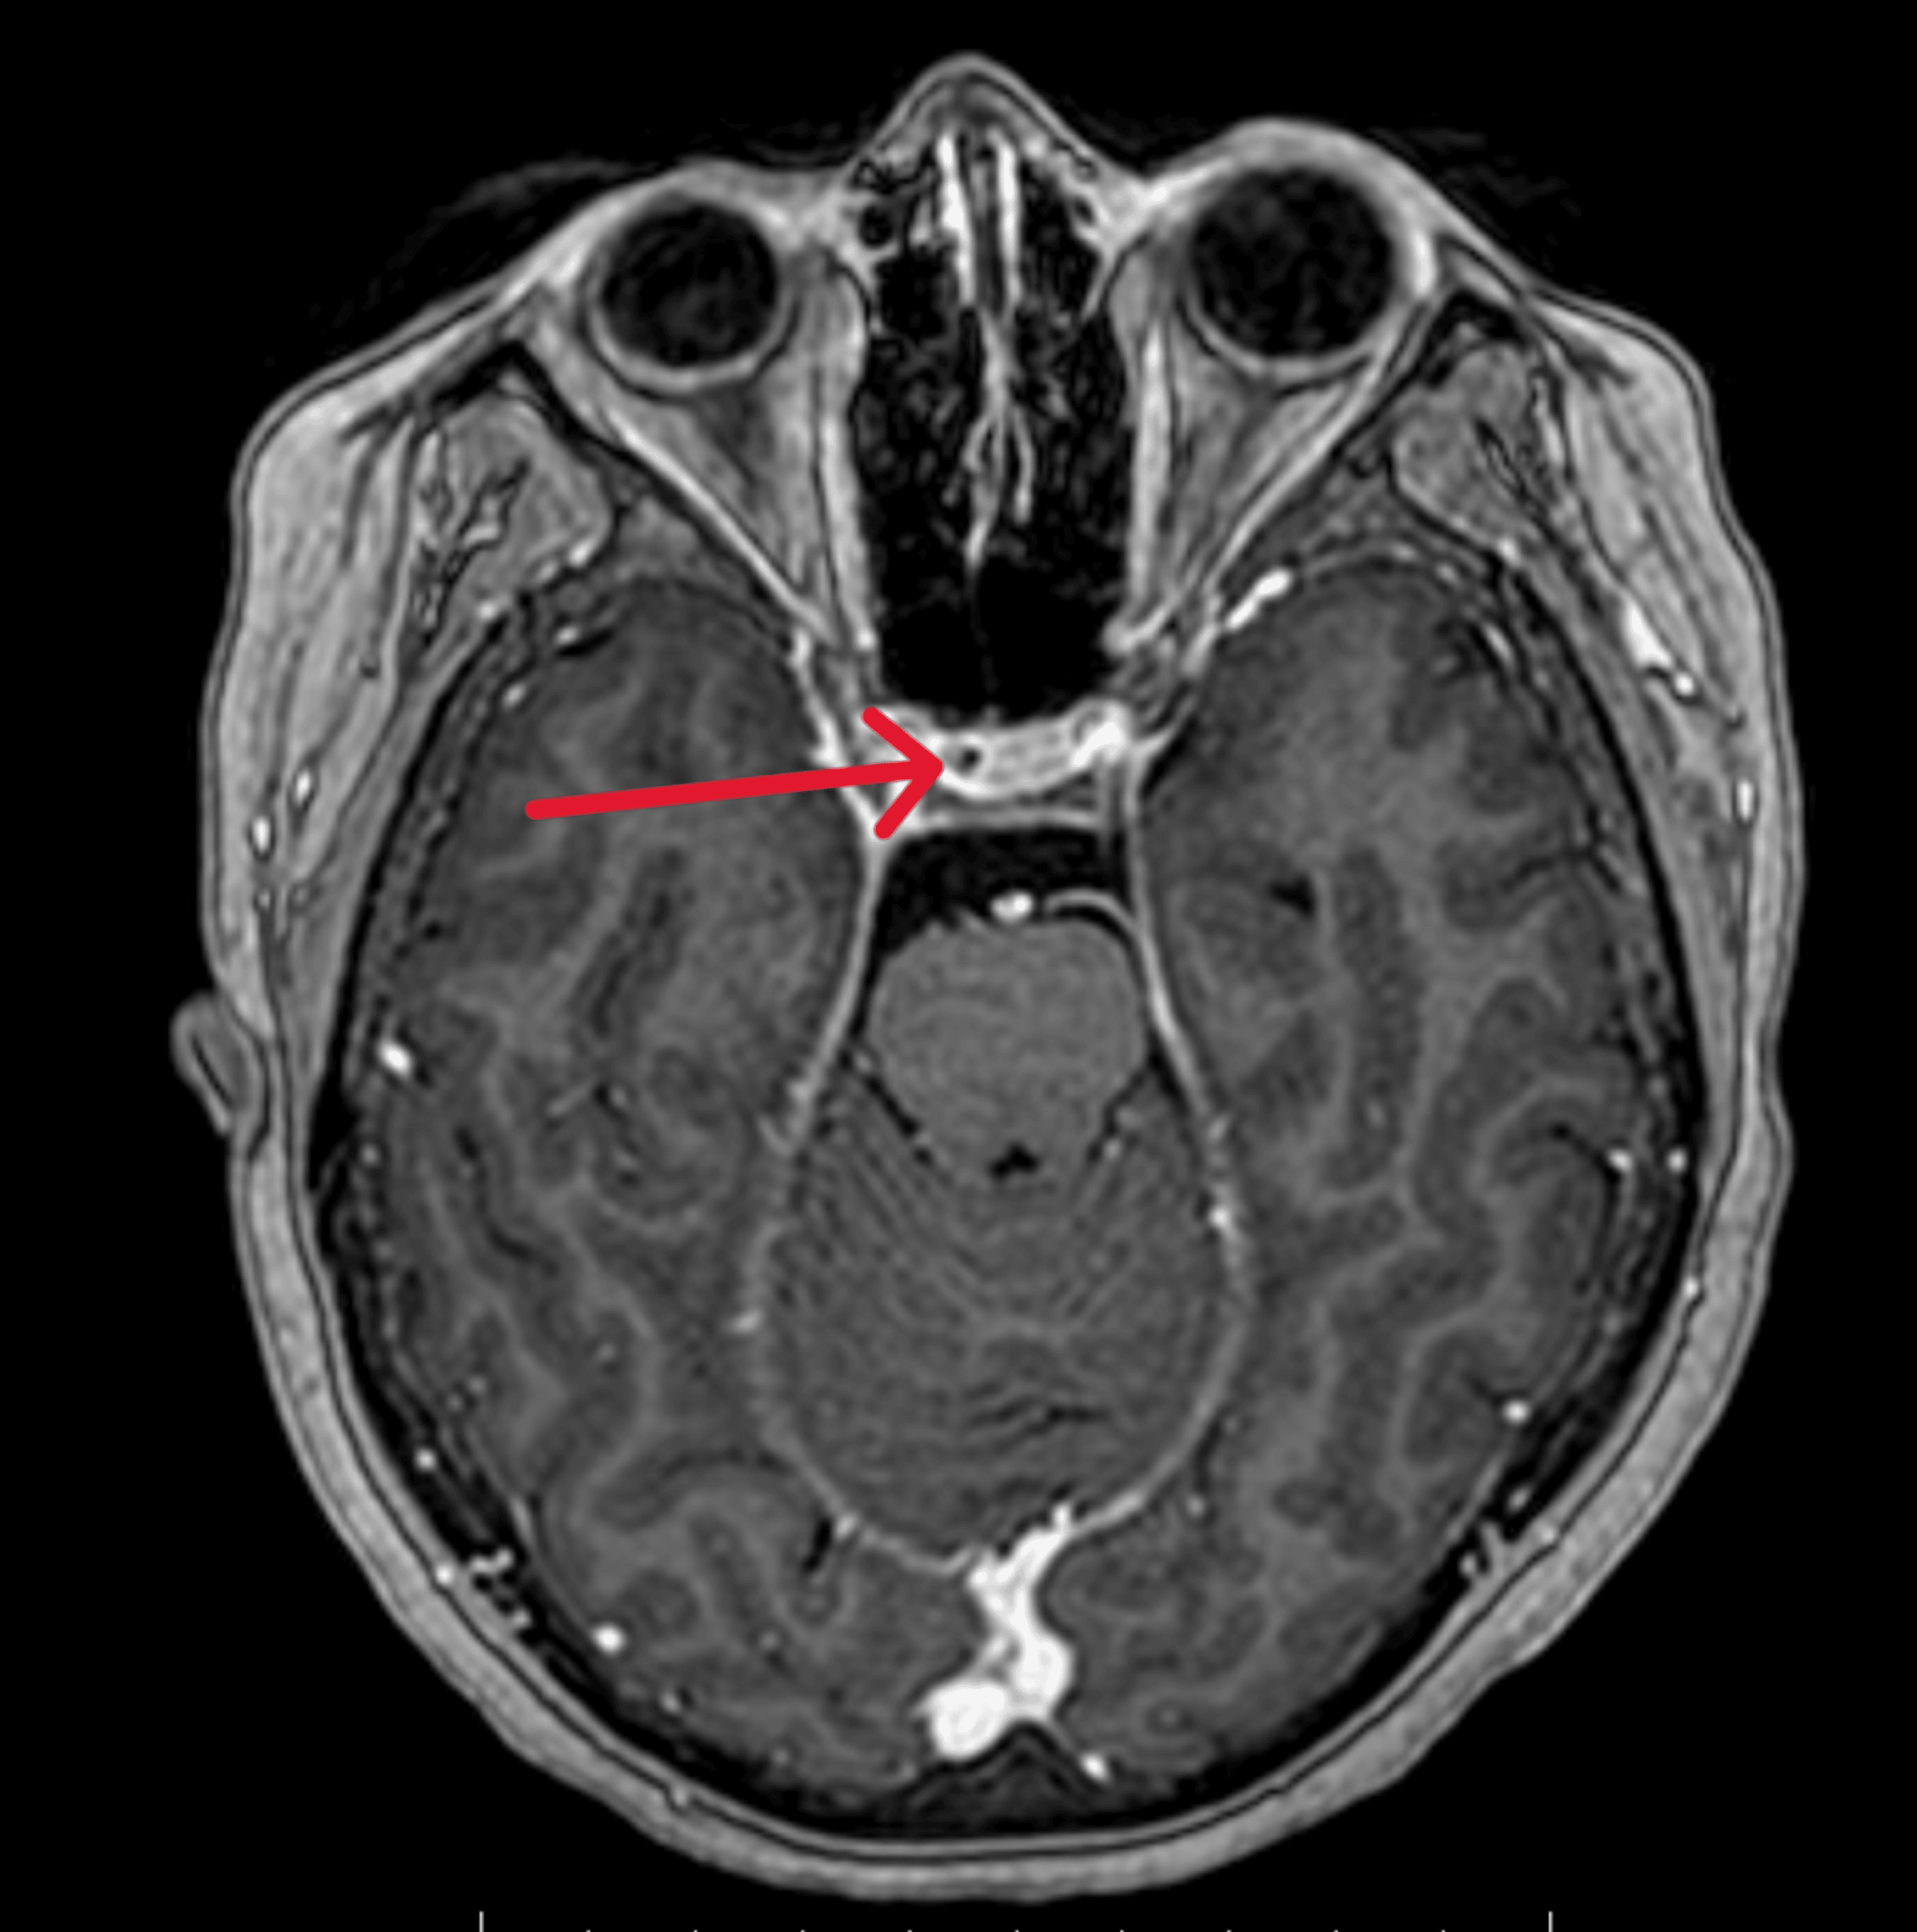

A Neurologist gave me Xanax. Since he couldn’t see my tumor with his Magnetic Resonance Imaging (MRI) machine there was “no possibility” that it existed. Boy was he wrong!

The MRI still showed nothing, so they did a Petrosal Sinus Sampling Test. That scared me more than the prospect of surgery. (This test carries the risk of stroke and uncontrollable bleeding from the incision points.) Catheters were fed from my groin area to my pituitary gland and dye was injected. I could watch the whole procedure on monitors. I could not move during this test or for several hours afterwards to prevent uncontrolable bleeding from a major artery. The test did show where the tumor probably was located. Also done were more sophisticated dexamethasone suppression tests where drugs were administered by IV and blood was drawn every hour (they put a heplock in my arm so they don’t have to keep sticking me). I got to go home for a weekend and then went back for the surgery – the Transsphenoidal Resection. I fully expected to die during surgery (and didn’t care if I did) so I signed my will and wrote last letters to those I wanted to say goodbye to. During the time I was home just before surgery, a college classmate of mine (I didn’t know her) did die at NIH of a Cushing’s-related problem. I’m so glad I didn’t find out until a couple months later!